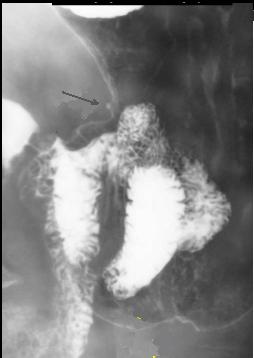

Adenocarcinoma de antre . Image en TOGD

de estomac .Le bord du tumeur est irregulie ,

rigidite et invasive |